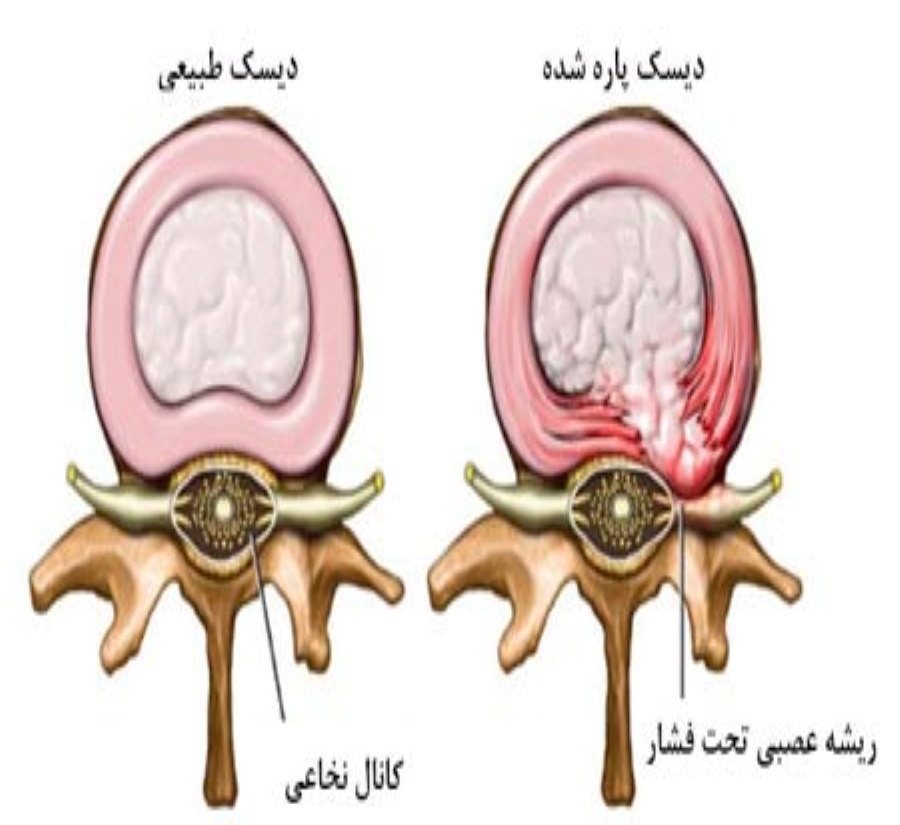

پارگی دیسک

علائم: پارگی دیسک کمر ممکن است بدون علامت بوده و یا با علائم زیر همراه باشد:

درد پشت، شکل غیر طبیعی ستون مهره ها، محدودیت حرکتی در ستون فقرات بخصوص خم شدن، نقص نورولوژیک در منطقه ی خاصی از اندامها، دردهای ناشی از آسیب عصبی، کاهش حس پوستی در اندام ها، کاهش یا فقدان رفلکس های تاندونی در اندام ها، گاهی اوقات ضعف و/یا تحلیل عضلانی.

علائم فوق معمولا یکطرفه اند ولی زمانی که دیسک دچار آسیب شدیدی در بخش مرکزی باشد و ریشه های عصبی دو طرف تحت تاثیر قرار گرفته باشند علائم بالینی دوطرفه دیده می شود.